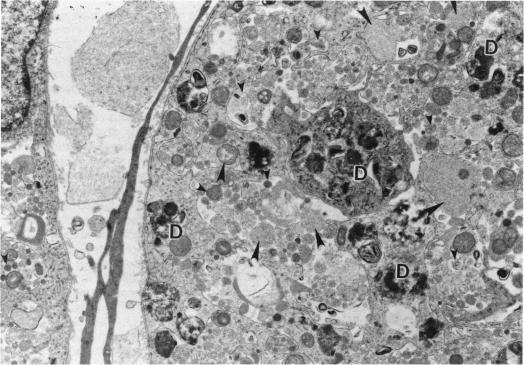

Male rats and male mice received a single 2-hr exposure to 0 (control), 10, or 30 ppm of methyl isocyanate and were sacrificed after 1, 3, 14, or 90 days to assess the ultrastructural changes in the nasal mucosa by transmission electron microscopy. One day after exposure to methyl isocyanate, there were widespread areas of necrosis and degeneration of the respiratory and olfactory epithelium of rats and mice in the 10 ppm and 30 ppm groups. Qualitatively the ultrastructural findings were similar for both exposure groups and species. Degeneration followed by rapid regeneration was observed for both respiratory and olfactory epithelia but was most striking for olfactory epithelium in the dorsal meatus. Three days after the exposure, the olfactory epithelium was two to three cell layers thick due to a loss of supporting cells, olfactory neurons, and basal cells. By 14 days after exposure, the olfactory epithelium was composed of a heterogeneous cell population three to five cell layers thick. At 90 days following exposure, the epithelium was of normal thickness (eight to ten cell layers), with normal architectural arrangement, and composed of well-differentiated cells that appeared similar to those of controls. There were several findings that suggested the epithelial cells of Bowman's glands were the progenitor for the regenerating supporting cells of the olfactory epithelium. This study demonstrated that the respiratory and olfactory epithelium is capable of complete structural regeneration after an acute destruction by methyl isocyanate.